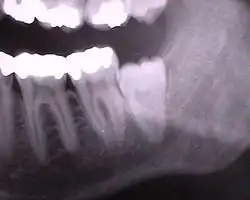

Die folgenden Röntgenbilder sind Ausschnitte aus Orthopantomogrammen (OPG):

-

Weisheitszähne 48 und 18; Zahn 48 – keine Kippung, Wurzel nur teilweise ausgebildet, Krone teilweise noch knöchern bedeckt

Weisheitszahn 38 angelegt; retiniert – Krone unter Zahn 37 verkeilt; Krone okklusal nicht mehr von Knochen bedeckt; nur eine Wurzel sichtbar – relativ kurz aber voll ausgebildet.

Weisheitszahn 38 angelegt – fast noch keine Wurzel ausgebildet; mesial gekippt.